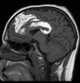

Ossification of falx cerebri